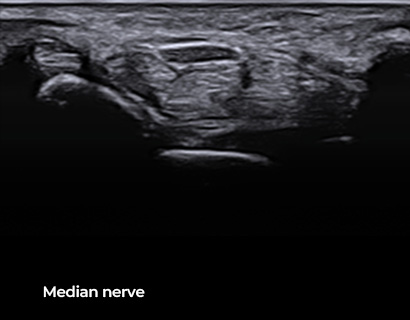

SL3-19H

X+ Crystal Signature™ linear transducer(3~19MHz)

Application:

MSK, Vascular, Small Parts, Breast, TCD, Abdomen, Pediatric, Gynecology, Obstetrics, EM